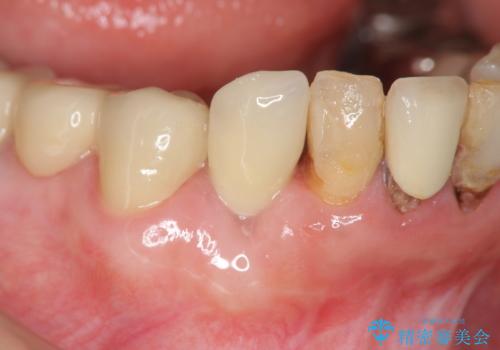

[ 上顎多数歯欠損 ] インプラント・義歯を用いた補綴

![[ 上顎多数歯欠損 ] インプラント・義歯を用いた補綴の症例 治療前](https://seimitsushinbi.jp/wp/wp-content/uploads/2020/09/df191d89bffff661c1e5377feed6ed49-500x350.jpg?v=1600566138)

![[ 上顎多数歯欠損 ] インプラント・義歯を用いた補綴の症例 治療後](https://seimitsushinbi.jp/wp/wp-content/uploads/2020/09/8be5dd778f94eb578b5490a0ba817f10-1-500x350.jpg?v=1600566164)